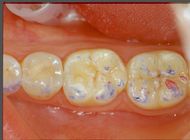

For this reason we bypass the manufacture of a bite plane to arrive directly at the definitive neurognathological prosthetic rehabilitation. In this specific case it was a Functional Neuro Evoked Centric rehabilitation of the anterior incisors and the four lower molars, two per side. The realization, however, followed some particularly obligatory pre-ordered steps which represent the best way to achieve real neuro-occlusal stability, as we will see in detail below. (figure 6)

In figure 6a we can see the structures of the crowns in the mouth on which the ceramic will be stratified and which will be covered with Aluvax wax to determine the Functional Neuro Evoked Centric. The decision to incorporate the four molars in the rehabilitation was made because these elements are crucial for occlusal stability but also for mediotrusion as we will see below. The exact mandibular position requires a third anterior point and for this reason, also considering the wear of the incisions and the importance of a normocclusion of the anterior sector, the involvement of the incisors was decisive for Centering the mandible in the optimal position (figure 6b) . Obviously, everything is brought back into articulate with mold waxes on Empress crowns. (figure 6c)